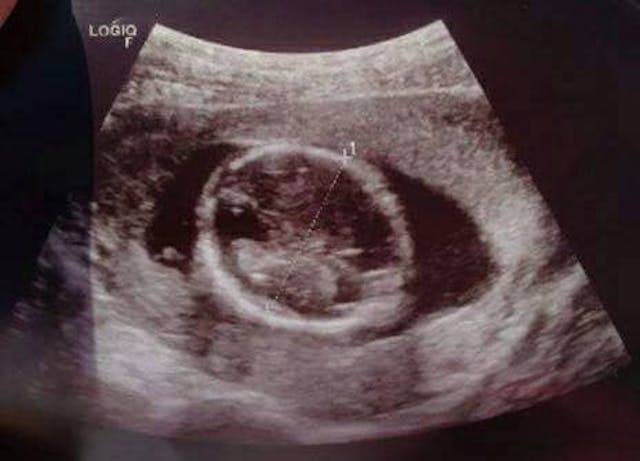

But when a would-be abortion patient stopped to talk to Pam outside the clinic after her consultation, it became clear, according to the woman’s explanation of what had just happened to her, that Planned Parenthood was not following the law. Pam asked the woman to show her the ultrasound Planned Parenthood had just performed on her. Below is the picture Planned Parenthood gave the woman considering abortion:

This is a picture of the baby from above, showing only the top of the child’s head. Planned Parenthood did not show her the full body of her baby. The woman seeing this picture had no idea that her baby already had very developed arms, legs, fingers, and toes (and had for weeks). The angle of the ultrasound prevented her from seeing these parts of the baby. All she saw was a circular blob — the top of the child’s head. This was the only part of the baby Planned Parenthood showed the woman (and probably all of the other women they saw that day). The woman had no idea her baby was fully developed. Planned Parenthood blatantly broke the law and deceived this woman.